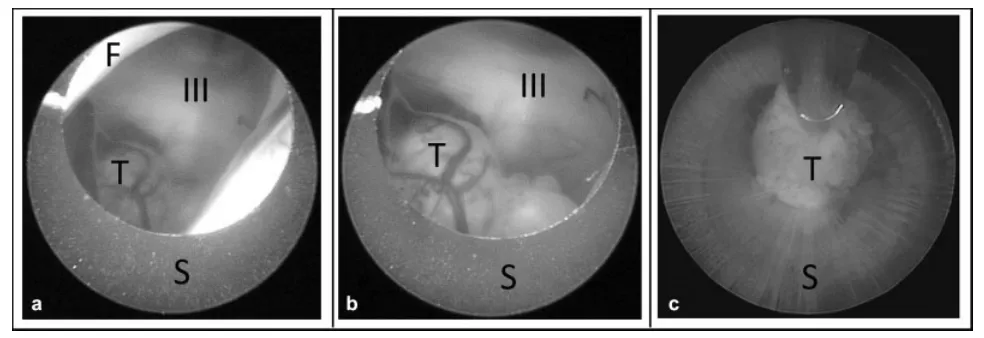

(a) 为观察鞘管边缘,将内镜向鞘管内回缩。 (b) 随后,在内镜直视下(观察穹窿、静脉及脉络丛以避免意外损伤),将鞘管引入第三脑室。 (c) 若肿瘤碎块过大无法通过主工作通道,术者可钳住肿瘤碎块,将其连同整个脑室镜一起从留置在脑内的鞘管中取出。缩写:III,第三脑室;F,穹窿;S,内镜鞘;T,肿瘤。